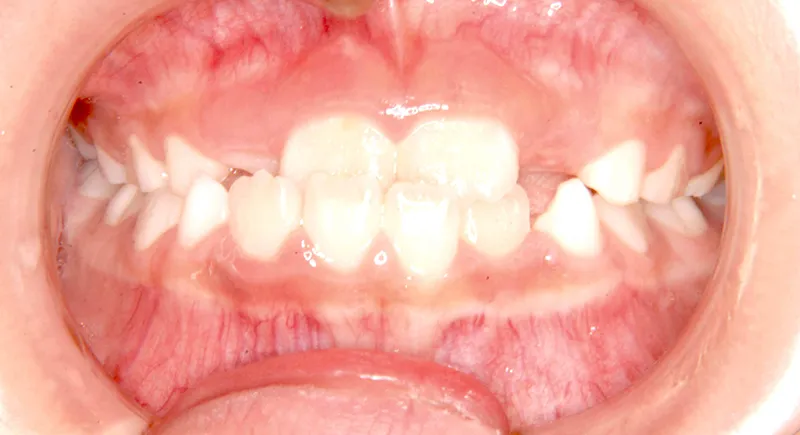

| 初診時年齢 | 小学校1年生(女性) | 主訴 | 受け口 | ||

| 診断名 | 叢生・反対咬合 | 装置名 | 拡大床 | ||

| 抜歯の有無 | 非抜歯 | 治療期間・通院回数 | 2年7ヶ月・21回 | ||

| 費用 | 481,890円(税込) | 費用内訳 | 相談料:1,050円 検査料:46,200円 施術料:210, 000円 装置料:105,000円 保定装置料:52,500円 調整料:3,150円×10回=31,500円 以上 消費税率5% / 調整料:3,240円×11回=35,640円 以上 消費税率8% | ブラケット・ ワイヤー |

付けずに治した |

| 特徴 |

固い食べ物が嫌い 乳歯列が綺麗に並んでいる ゆがんで生えている よく噛まないで飲み込む |

| 状態 |

永久歯が生える隙間がない(叢生) 受け口(口元が出ている/下顎前突/反対咬合) |

| リスク・副作用 |

矯正歯科治療に伴う一般的なリスク・副作用

|